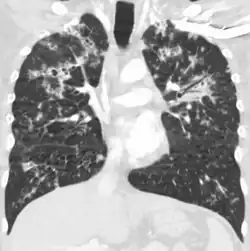

A case of miliary tuberculosis in an 82-year-old woman:

-

X-ray, 13 days after onset, showing bilateral interstitial infiltrates -

CT, 16 days after onset, showing extensive pulmonary parenchymal involvement consisting of irregular septal thickenings with ground-glass areas and centrilobular nodules with a peri-lymphatic distribution -